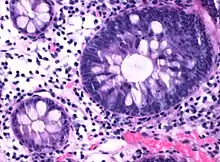

| Micrograph of hyperplastic polyp. | |

Histopathologically, there are two main types of hyperplastic polyps, which have genetic differences, as well as different histologic structure, but no significant differences clinically.[4] The two main types of hyperplastic polyps are microvesicular mucin-rich type and goblet cell-rich type.[1] A mucin-poor type with eosinophilic cytoplasm, which is rare, was previously described.[4] However, the mucin poor type is no longer considered a distinct subtype.[1]

Mucin-rich type

The luminal portion has a serrated (“saw tooth”) appearance formed by tufts or folds of abundant apical cytoplasm. It contains glands with star-shaped lumina.[4] There are crypts that are elongated but straight, narrow and hyperchromatic at the base. All crypts reach to the muscularis mucosae.[4] The basement membrane is frequently thickened.[4]

Goblet cell-rich type

Elongated, fat crypts and little to no serration. Therefore, they may not be obvious without comparing to adjacent normal intestinal wall.[4]

They are filled with goblet cells, extending to surface, which commonly has a tufted appearance.[4]